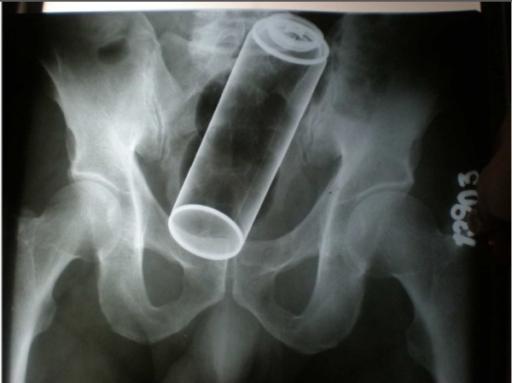

Management of rectal foreign bodies. Coskun A, Erkan N, Yakan S, Yıldirim M, Cengiz F - World journal of emergency surgery : WJES (2013)